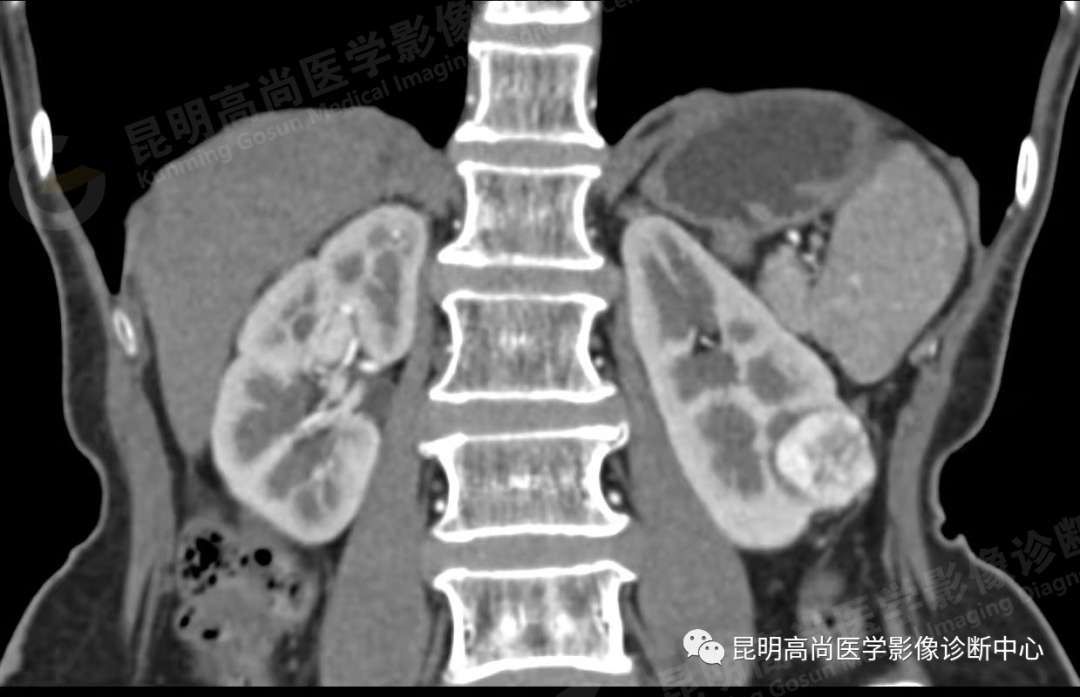

于 2021 年 9 月 17 日至本中心行 CT 平扫+增强检查;

左肾下份占位病变,多考虑恶性肿瘤。请结合临床及相关检查。

能清晰地显示直径 1 cm 以上肾实质内肿块,肿瘤边缘不规整,呈圆形或分叶状;

平扫时,肿瘤的密度随肿瘤的细胞成分不同而略有差异,透明细胞癌的密度低于正常肾实质,而颗粒细胞癌的密度略高于正常;

增强扫描后,肿瘤密度可不同程度地增强,但仍低于正常肾组织,由于增加了肿瘤与肾组织间的密度差,可以更清楚地显示肿瘤大小与分界线;

肿瘤内常有出血、液化和坏死区,使瘤体密度变为不均性;5%-10% 肿瘤内可见密度增强的钙化灶,位于瘤体中央或边缘处;

CT 对肾细胞癌能精确估计病变的大小和范围,还可了解周围有无浸润、淋巴及远处有无转移,从而对肾癌的分期提供重要的依据。